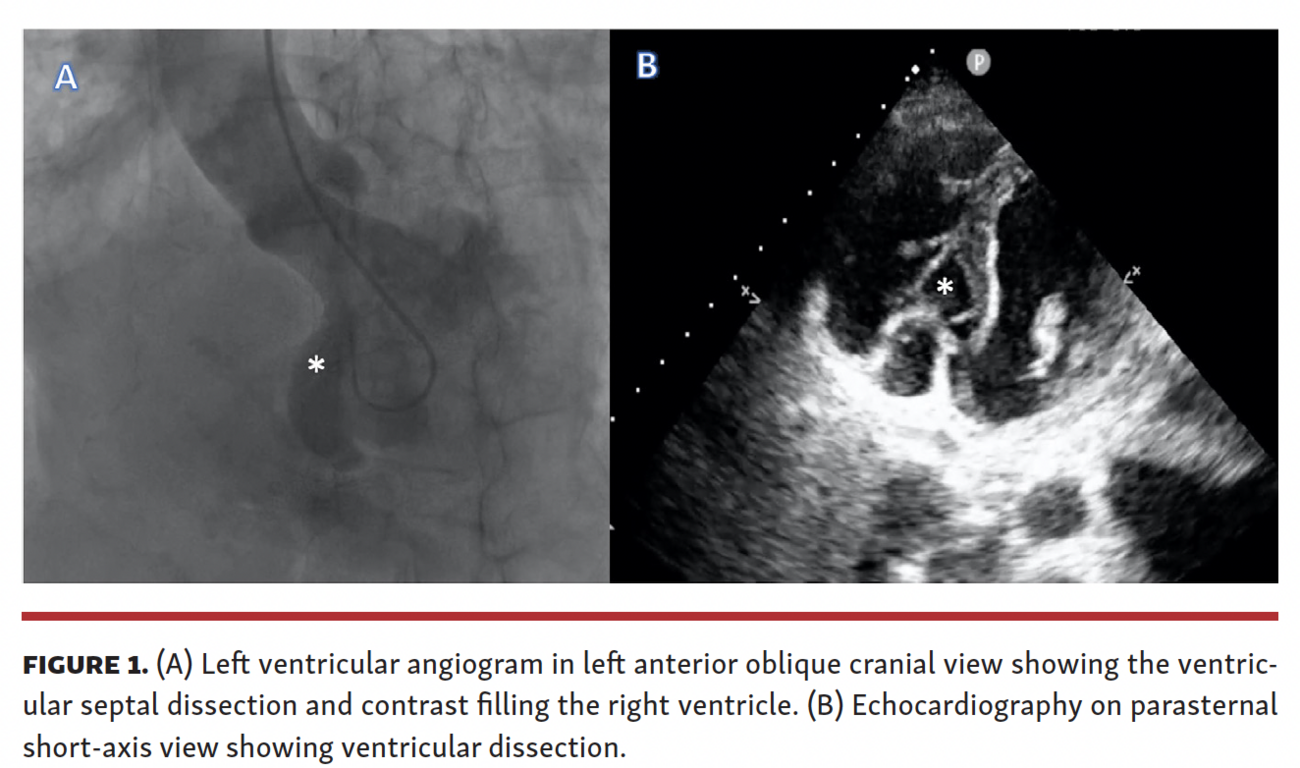

A 57-year-old female patient presented to the emergency room with acute-onset dyspnea for 2 days. She was thrombolyzed with streptokinase 4 days prior for inferior wall myocardial infarction (MI) in a nearby hospital. Her exam showed elevated jugular venous pressure and systolic murmur in the left lower parasternal region. Electrocardiogram showed Q waves in inferior leads. Echocardiography (Figure 1B; Video 1) showed an akinetic inferior wall. In addition, there was a ventricular septal rupture in the posterobasal interventricular septum, with at least 2 exit points into the right ventricle. The posterobasal appeared to have dissected, leading to communication between the left and right ventricles. Coronary angiography showed a normal left coronary artery and complete occlusion of the right coronary artery (RCA). There were no collaterals from the left system to the RCA. Left ventricular angiogram (Figure 1A; Video 1) was done with a pigtail catheter, which showed ventricular septal defect with diffuse contrast filling of the right ventricle. This was suggestive of multiple entry points into the right ventricle. Since there were multiple exit points, device closure could not be contemplated. The patient was stabilized with optimal medical therapy and planned for ventricular septal repair after 28 days, as in the immediate aftermath of ST-segment elevation MI, the septum will be friable and increase the difficulty of suture application. The patient underwent patch repair elsewhere and is currently doing well.